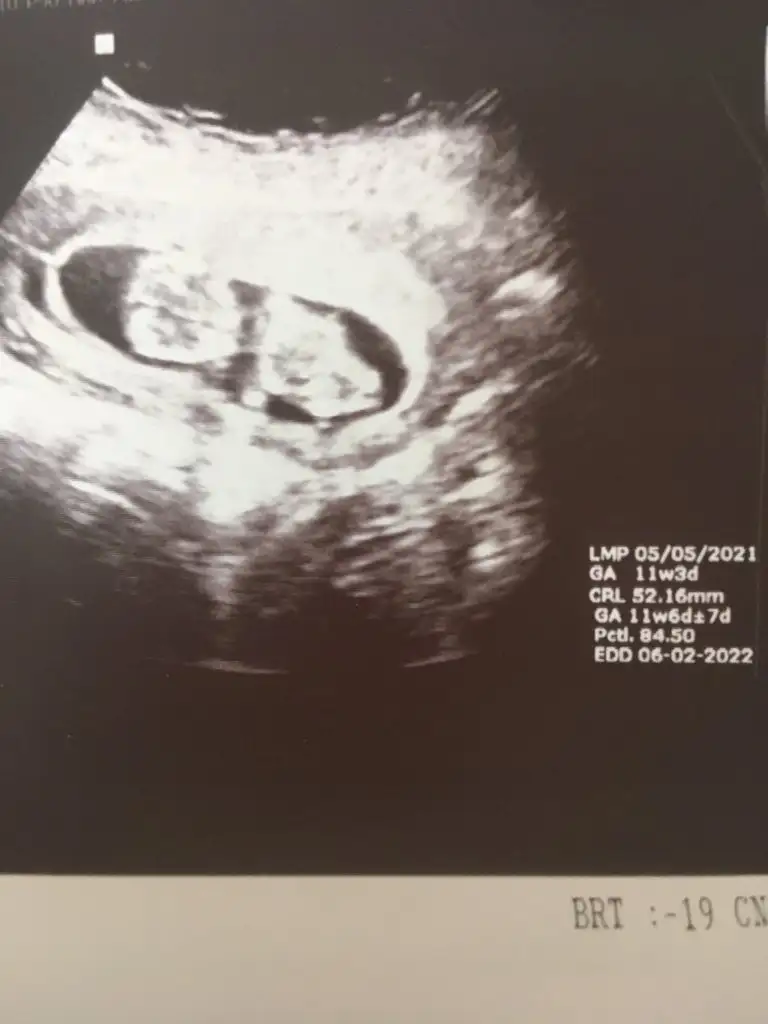

Kız gibi sanki emin olamadımEki Görüntüle 2892053 Eki Görüntüle 2892054 @Ikra meyra acaba müsait olunca bakar mısın? 11+6 oldu belli olur mu biraz?

Teşekkür ederimKız gibi sanki emin olamadım

Bugün cinsiyetini öğrendik,kızımız olacak. Teşekkürler zaman ayırdığınız için.Erkek gibi sanki

Sağlıkla gelsin prensesBugün cinsiyetini öğrendik,kızımız olacak. Teşekkürler zaman ayırdığınız için.